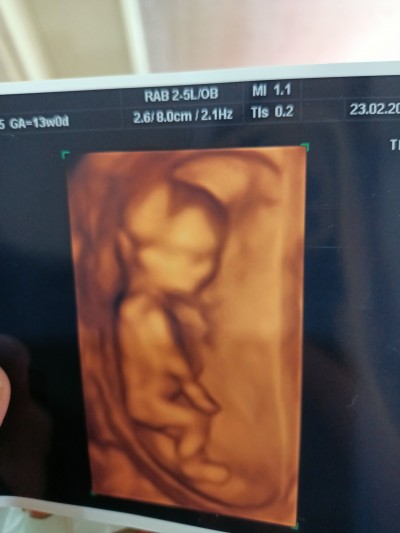

Kızlar merhaba cinsiyette kemik yapısı neye göre erkek veya kız olabiliyor nasıl anlaşılıyor bilen var mı?Mesela benim bebeğimin ultrasonu nasıl anlayacağız

Erkeke benzio kafasi yuvarlasa kiz

Arni düzse erkek diolarya dogrumu tam bilemedim

Erkeğe benziyor cnm vücut yapısından kafa yapisindan da anlaşılabiliyor

Merak ettimxe hangi hastaneye gidiyorsunuz acaba ultrasyon cihazi çok iyi ve net